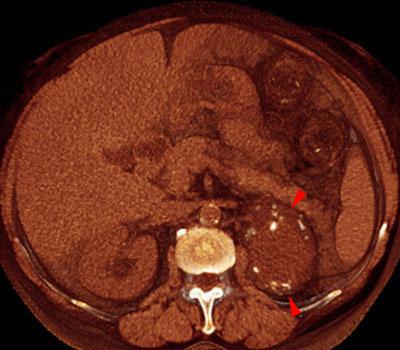

Quiste renal calcificado

VR seccional. Visión axial caudal. Estudio no contrastado que muestra, por detrás de la cola del páncreas, una lesión quística (puntas de flecha) con calcificaciones en su periferia